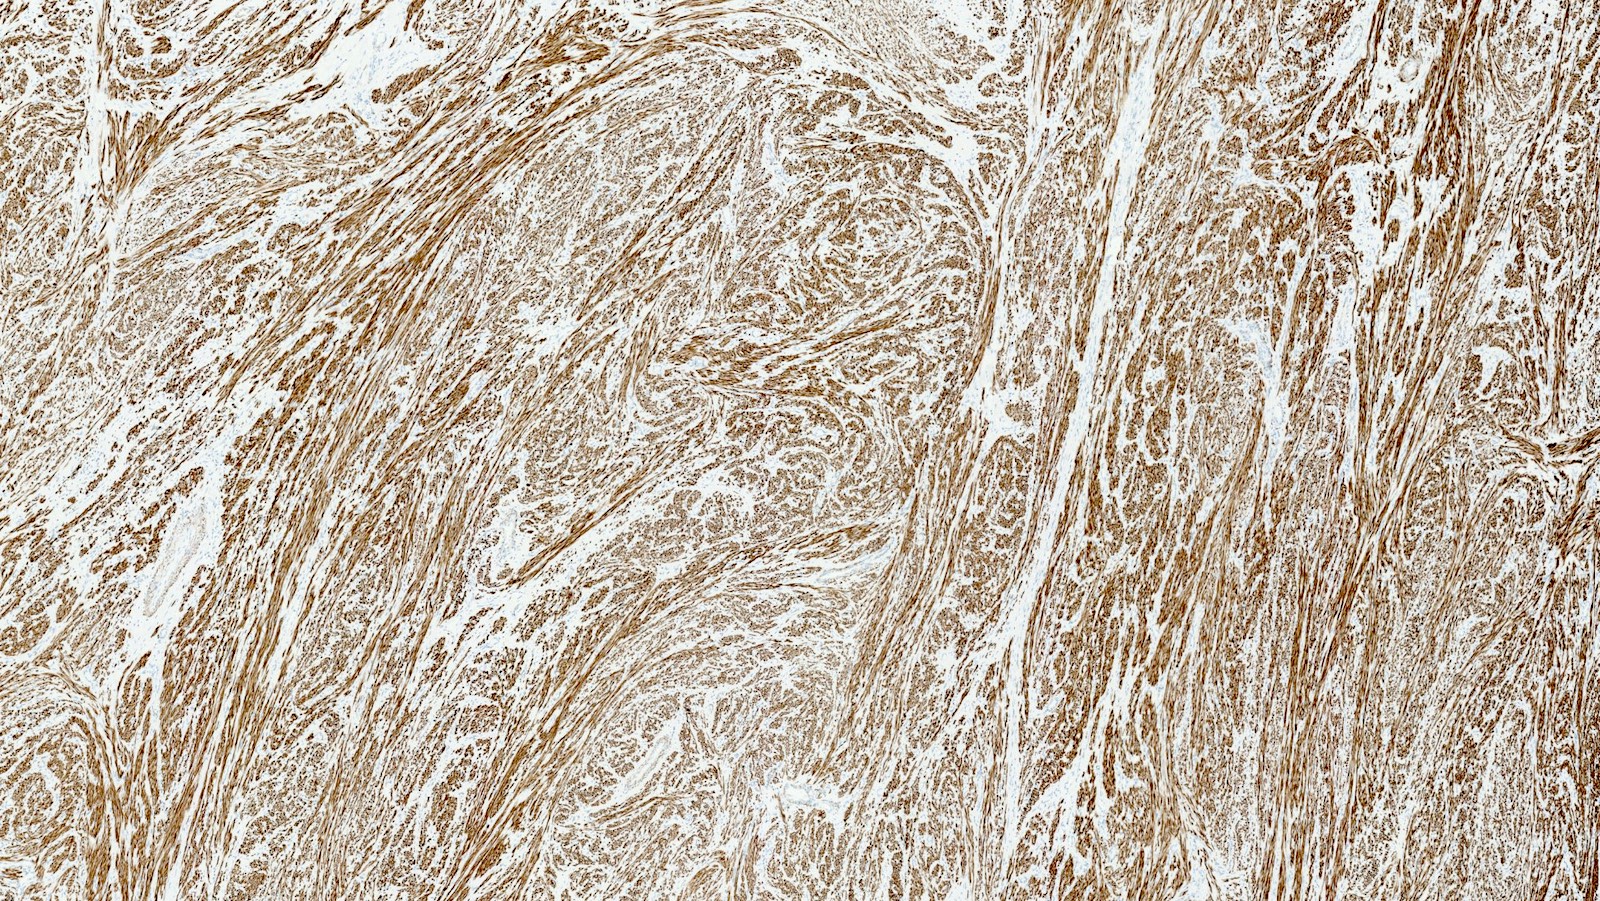

Positive stains

- Desmin

- h-caldesmon

- Smooth muscle actin

- Transgelin

- Smooth muscle markers can be weak in epithelioid and myxoid leiomyomas

- Estrogen and progesterone receptors

- WT1

- Up to 40% of leiomyomas are CD10 positive (especially cellular leiomyomas) (Am J Surg Pathol 2002;26:403)

Microscopic (histologic) images

Contributed by Sabrina Croce, M.D., Ph.D., Kristina Doytcheva, M.D., Jennifer A. Bennett, M.D. (Case #508) and @Andrew_Fltv on Twitter

- Comment: Microscopic examination reveals a smooth muscle tumor composed of spindle, cigar shaped cells arranged in fascicular pattern without cytologic atypia and tumor cell necrosis. Mitoses are rare (4 mitoses/10 high power fields). Tumor borders are well circumscribed. By immunohistochemistry the tumor cells are positive for desmin, h-caldesmon, ER and PR.